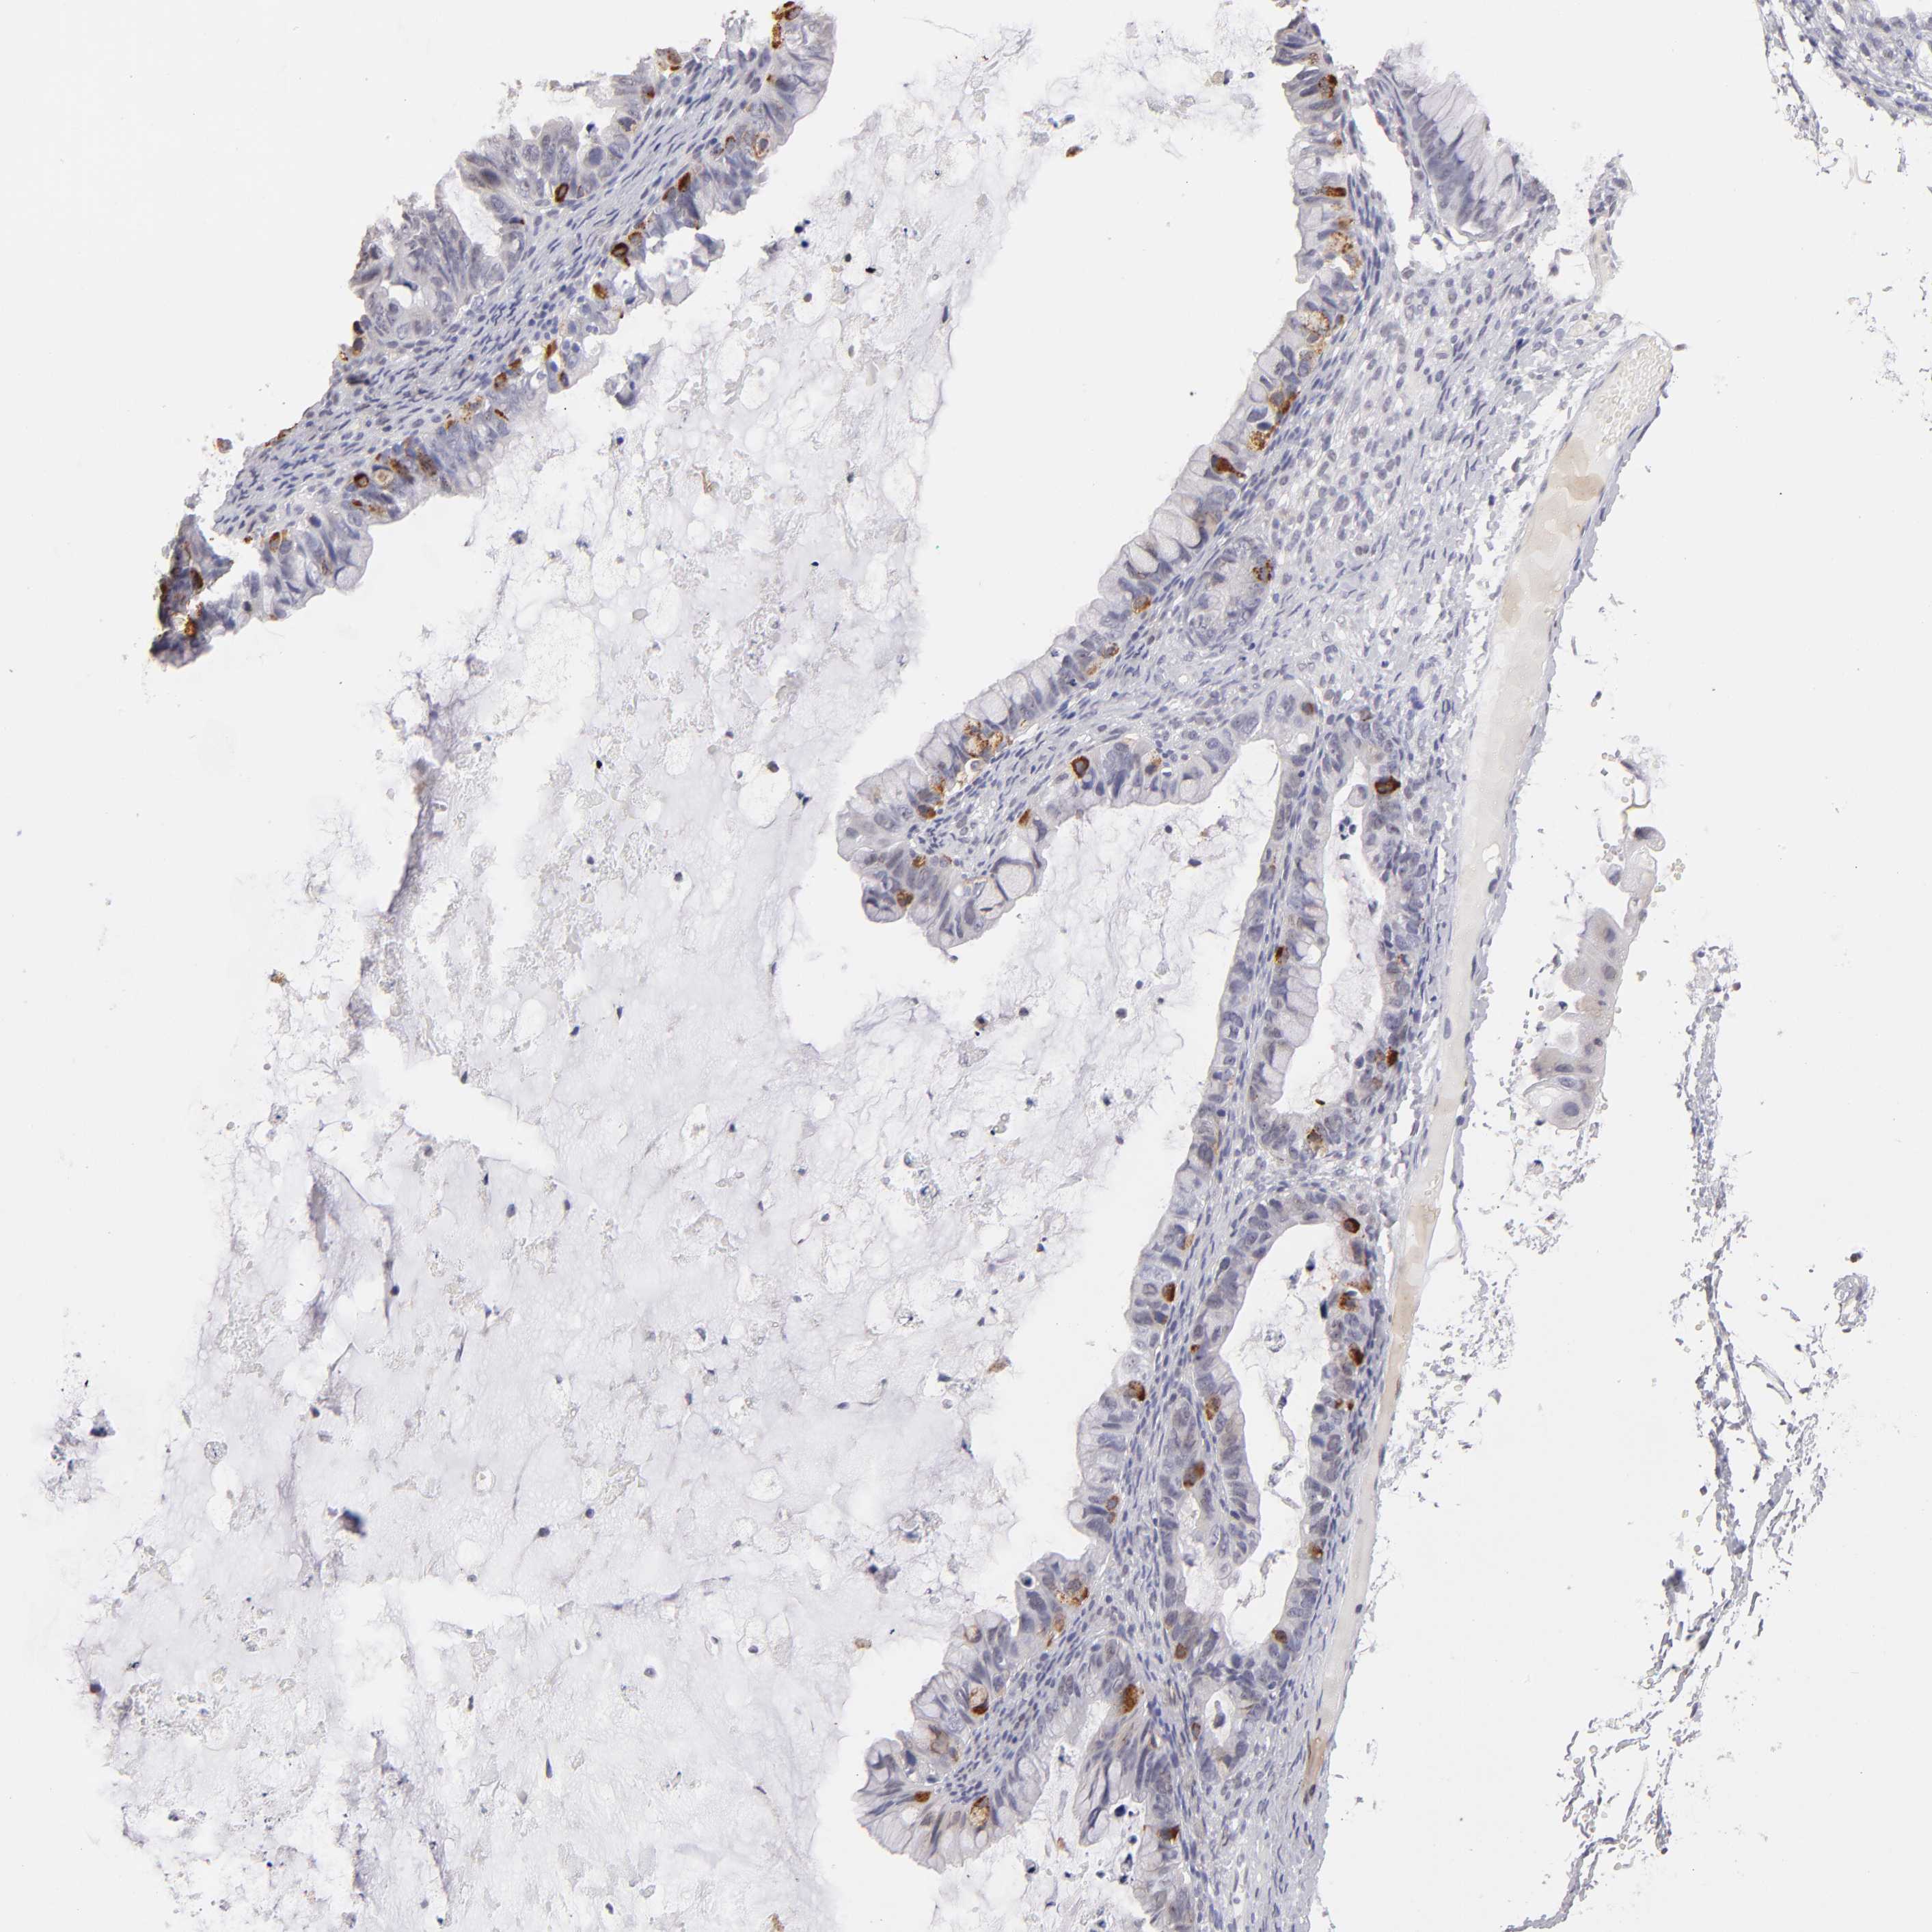

OVARIAN CANCER - Protein expressioni

A mouse-over function shows sample information and annotation data. Click on an image to view it in a full screen mode. Samples can be filtered based on level of antibody staining by selecting one or several of the following categories: high, medium, low and not detected. The assay and annotation is described here.

Note that samples used for immunohistochemistry by the Human Protein Atlas do not correspond to samples in the TCGA dataset.

Antibody stainingi

Antibody staining in the annotated cell types in the current human tissue is reported as not detected, low, medium, or high, based on conventional immunohistochemistry profiling in selected tissues. This score is based on the combination of the staining intensity and fraction of stained cells.

Each image is clickable and will lead to virtual microscopy that enables deeper exploration of all samples and also displays staining intensity scores, fraction scores and subcellular localization as well as patient and tissue information for each sample.

Antibody HPA002270

Staining

High

Medium

Low

Not detected

Intensity

Strong

Moderate

Weak

Negative

Quantity

>75%

75%-25%

<25%

None

Location

Nuclear

Cytoplasmic/membranous

Cytoplasmic/membranous,nuclear

Cystadenocarcinoma, serous, NOS

Cystadenocarcinoma, mucinous, NOS

Carcinoma, endometroid